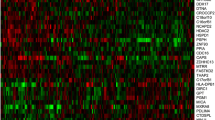

In the Carolina Breast Cancer Study, 32% of participants were classified as HGF-positive by our 38-gene assay. Clustering the HGF signature genes across all of the CBCS patients, we found two main gene clusters that corresponded well with expression patterns from the original reference signature [9]. Specifically, HGF-positive tumors had few (n = 6) genes highly expressed, while most genes had a characteristic pattern of lower expression (Fig. 1). TNBC samples were enriched in the HGF-positive cluster.